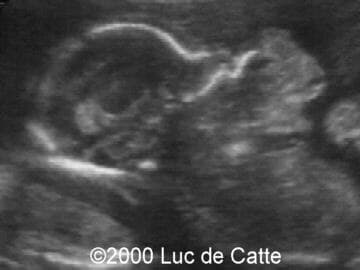

The following structural defects were observed:

• anterior mass,

• emanating from the fetal mouth,

• partly cystic, partly solid

• no calcifications

This 32-year-old primigravida patient was referred at the ultrasound department at 19.5 weeks of gestation for a second opinion concerning a fetal facial mass. Scanning revealed a large, mixed tumor emanating from the pharynx and mouth. The fetal position did not allow for other congenital anomalies to be observed. The diagnosis of epignathus was made.

Epignathus (from the greek epi = above and gnaqos = jaw) represents a rare congenital teratoma arising from the palate or pharynx in the region of the sphenoid (Rathke's pouch)1,2. It may involve the sphenoid bone, pharynx, tongue and jaw. Although it may vary greatly in size and texture, epignathus generally extends through the mouth and creates an anterior facial mass. There is no known genetic or recurrence risk or predisposing factors.

Most are diagnosed by ultrasound scanning in the late second and third trimesters, although early diagnosis at 151 and 17 weeks of gestation3 have been reported. A large mixed solid-cystic and sometimes calcified tumor projecting from the oral cavity suggests the diagnosis. Because the tumor can interfere with swallowing, polyhydramnios can be present3. Occasionally, a large and vascular epignathus may lead to high-output cardiac failure and subsequently to a non-immune hydrops fetalis.